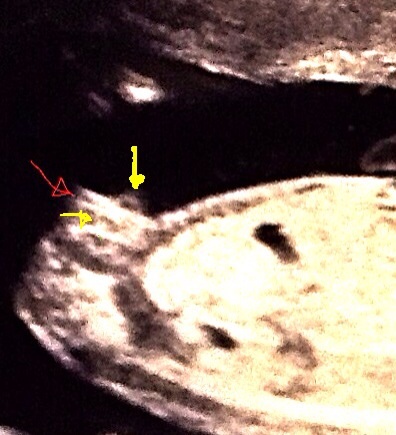

Attachment 13240Find out in 3 weeks for sure!

I would guess girl

girl